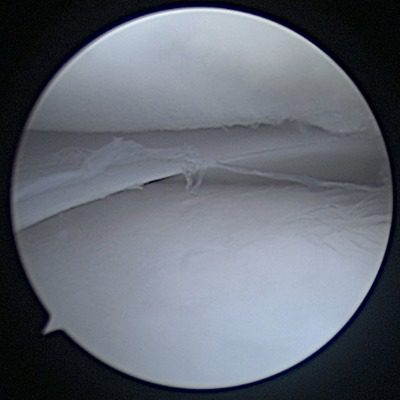

Partial Cranial Cruciate Ligament Tear